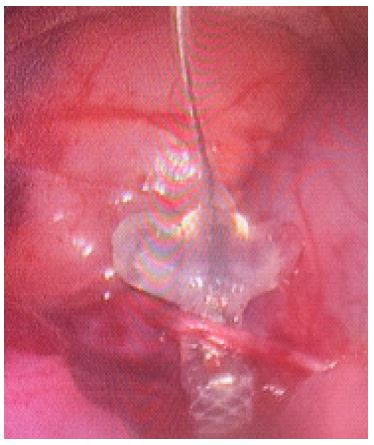

On June 20, 2021, under the thoracoscopic guidance separated the right nervus phrenicus with the fixation of the Diaphragm Pacemaker on it (Figure 2).

Figure 2: Thoracoscopy. Applying of pacemaker.